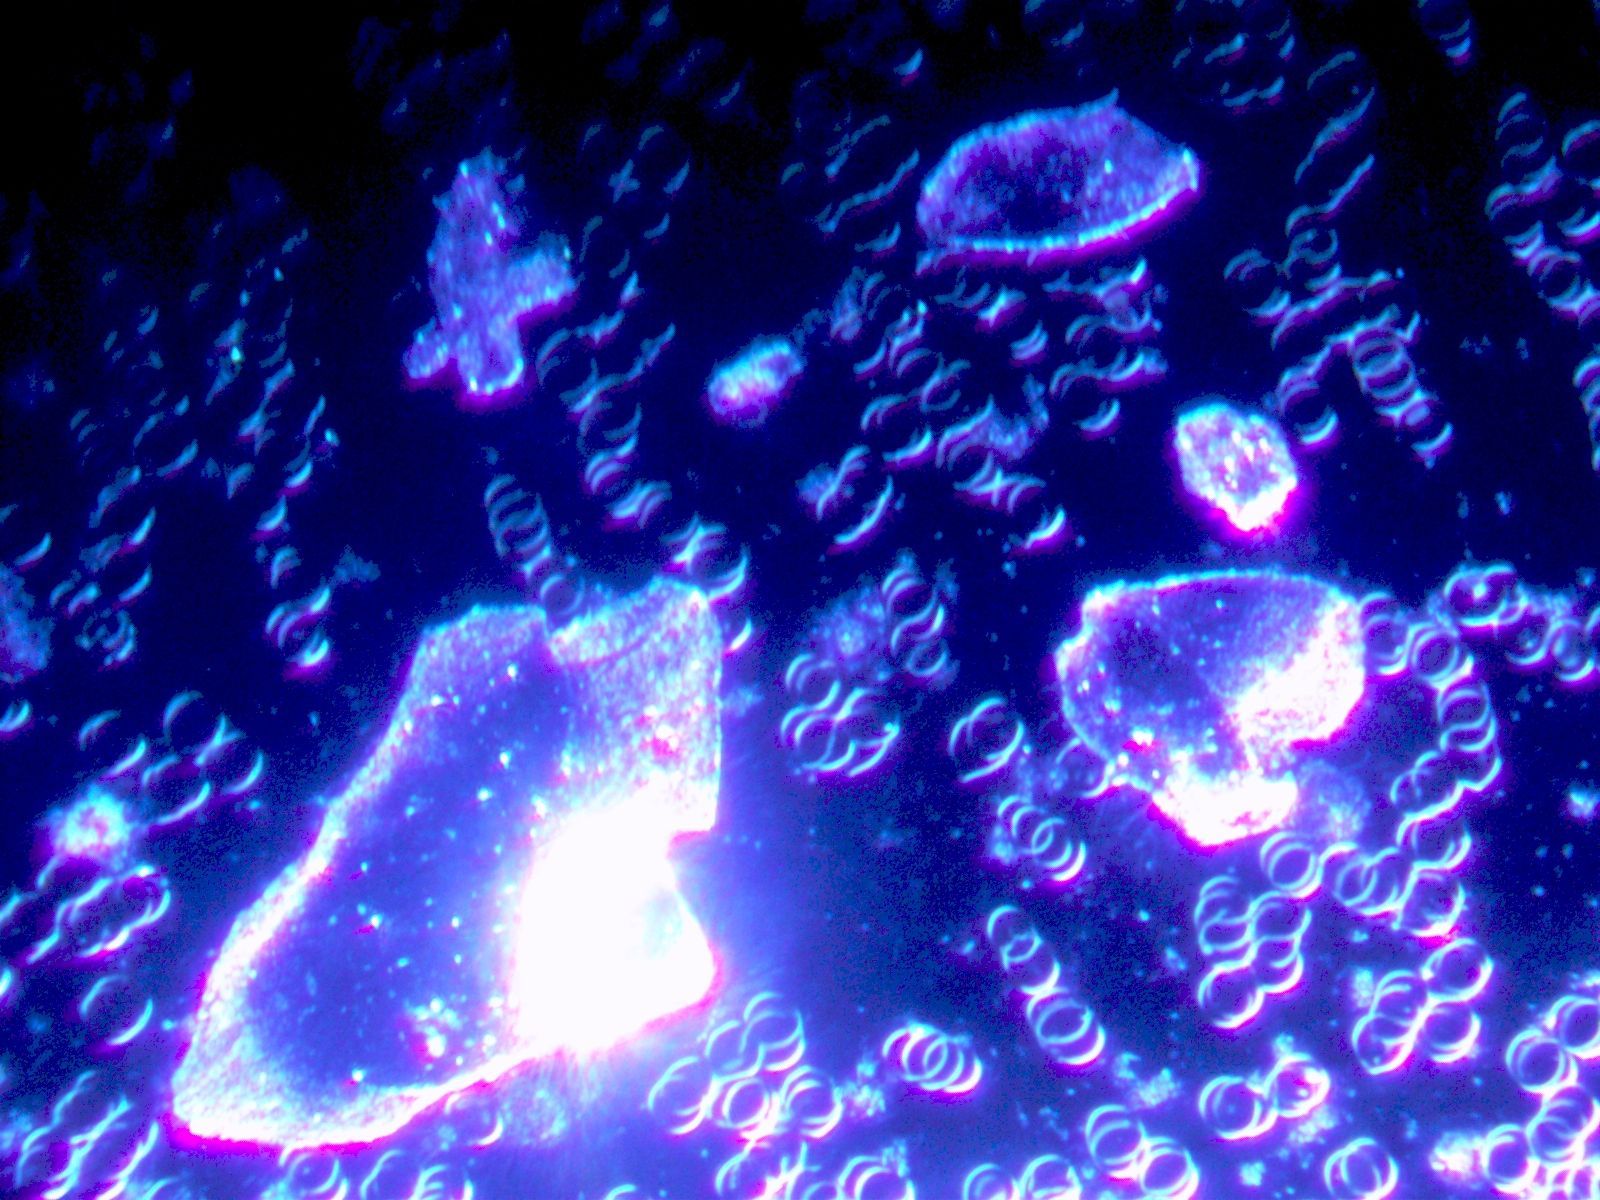

Die Dunkelfeldmikroskopie

Die Dunkelfeldmikroskopie ist eine spezielle Variante der Lichtmikrosokopie. Diese spezielle Untersuchungsmethode des Vitalbluts gibt tiefe Einblicke in die biochemischen Prozesse des Körpers und ist eine ideale Ergänzung, sowohl zu den herkömmlichen schulmedizinischen Laborblutbefunden, als auch zur bioenergetischen Körpermessung mit Global Diagnostics / Vitalfeldtherapie.

Während bei den üblichen Labor-Blutbildern die Bestandteile des Blutes quantitativ bestimmt werden, zeigt das Dunkelfeld Aktionen und Interaktionen der Blutzellen, sowie deren Form und Beschaffenheit. Dies ermöglicht nicht nur Beurteilung von akuten Erkrankungen, sondern auch Dispositionen für gesundheitliche Probleme, bevor sie sich in Symptomen manifestieren.

Für die Dunkelfeldmikroskopie genügt ein einziger Blutstropfen aus der Fingerbeere. Dieser wird in Ihrem Beisein über das Dunkelfeldmikroskop analysiert und in Echtzeit zum Mitschauen auf einen Bildschirm übertragen -Bei vorliegenden Belastungen können wir in einem gemeinsamen Gespräch ein grundlegendes Therapiekonzept entwickeln.